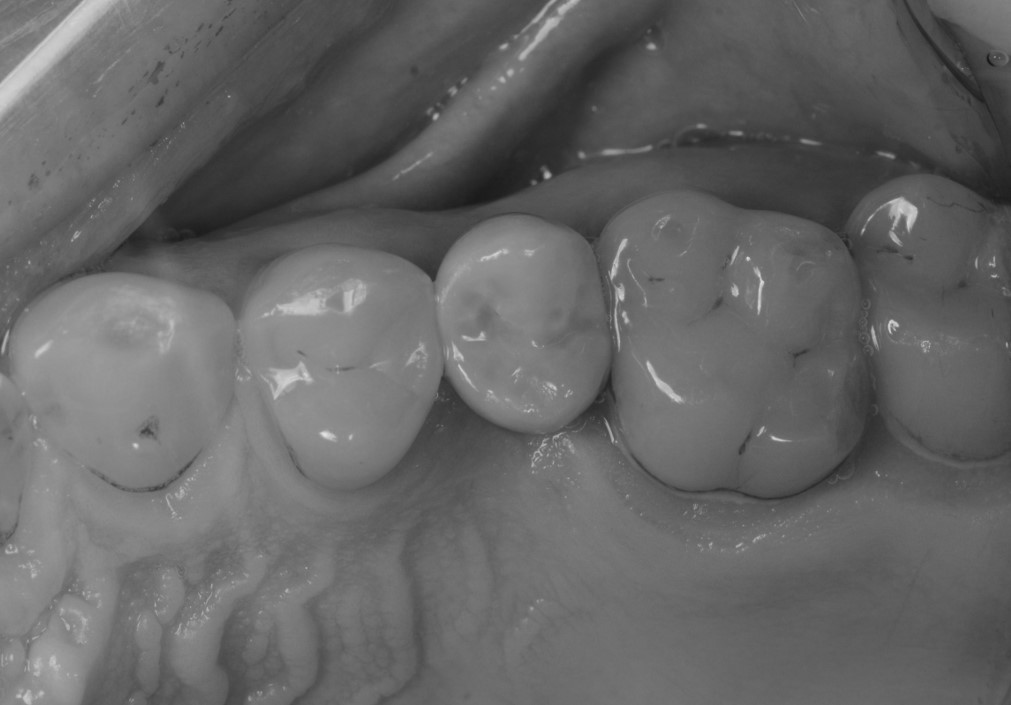

Situazione pre-operatoria, visione occlusale

Fig. 2. Situazione pre-operatoria, visione occlusale. Il secondo premolare di sinistra (#25) è stato da poco estratto perché non più recuperabile e il paziente.